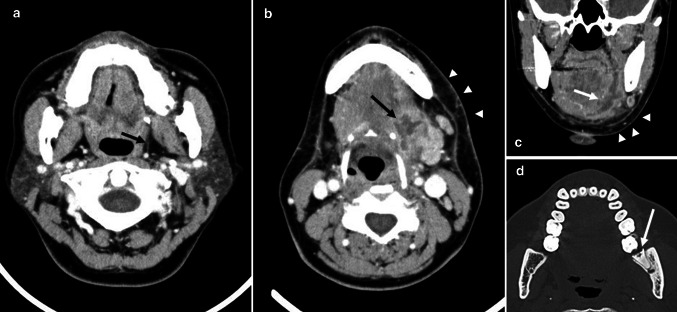

Fig. 1.

A 47-year-old woman with odontogenic infections. a Axial contrast-enhanced CT image demonstrates no spread of odontogenic infections in parapharyngeal space (arrow). b Axial contrast-enhanced CT image demonstrates abscess in sublingual space (arrow) and the spread of odontogenic infections in submandibular space (arrowheads). c Coronal contrast-enhanced CT image demonstrates abscess in sublingual space (arrow) and the spread of odontogenic infections in submandibular space (arrowheads). d Axial bone-algorithm CT image demonstrates pericoronitis (arrow)